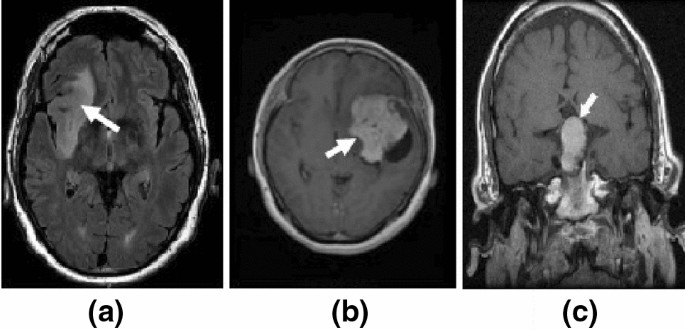

MRI of the brain in a 37-year-old man with sarcoidosis who had loss of vision in the right eye and blurry vision in the left eye. Ad The various symptoms of Sarcoidosis can successfully be treated. It is a long-term chronic disease of the central nervous system which encompasses the brain spinal cord and optic nerve and is characterized by inflammation within one or more of those areas.

Extrapulmonary Sarcoidosis With A Focus On Cardiac Nervous System And Ocular Involvement Eclinicalmedicine